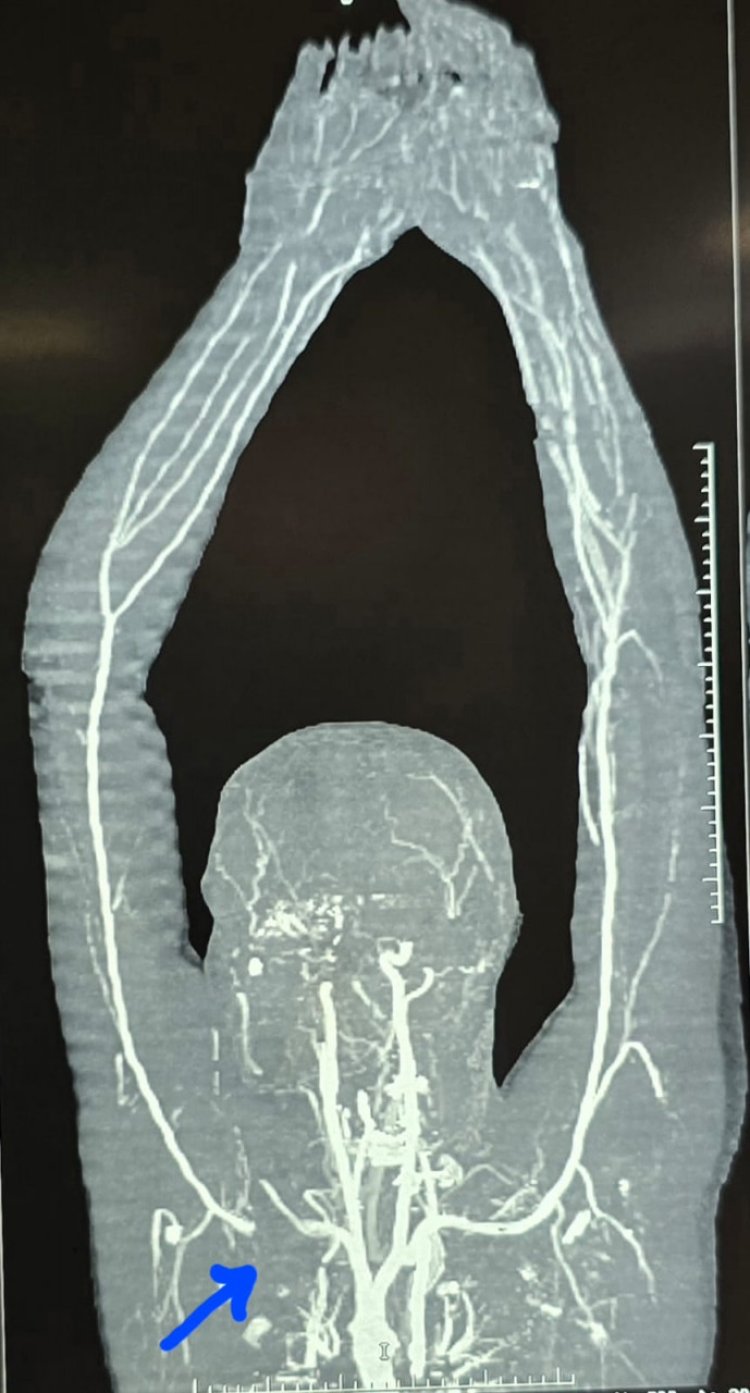

पंडित जवाहरलाल नेहरू स्मृति चिकित्सा महाविद्यालय एवं डॉ. भीमराव अम्बेडकर स्मृति चिकित्सालय (मेकाहारा), रायपुर के डॉक्टरों ने एक बार फिर जटिल और जानलेवा केस की जटिल एवं सफलतापूर्वक सर्जरी कर घायल मरीज के हाथ को कटने से बचाया। डॉक्टरों के अनुसार, यदि मरीज को समय पर इस प्रकार की जटिल शल्य- चिकित्सा की सुविधा नहीं मिलती तो मरीज के हाथ कटने की नौबत आ जाती और मरीज दिव्यांग हो जाता। हार्ट- चेस्ट और वैस्कुलर सर्जरी विभागाध्यक्ष डॉ. कृष्णकांत साहू के नेतृत्व में एक युवक के कंधे पर चाकू से हुए हमले में बुरी तरह क्षतिग्रस्त मुख्य रक्त नली (सबक्लेवियन आर्टरी) को जोड़कर डॉक्टरों की टीम ने न केवल मरीज की जान बचाई, बल्कि उसका हाथ कटने से भी बचा लिया। इस सर्जरी की एक और विशेष बात यह रही कि इसमें ऑर्थोपेडिक सर्जन भी शामिल रहे जिनकी मदद से कॉलर बोन को काटा गया एवं ऑपरेशन के बाद वापस प्लेट लगाकर जोड़ दिया गया।

इस केस की विस्तृत जानकारी देते हुए विभागाध्यक्ष (हार्ट- चेस्ट और वैस्कुलर सर्जरी) डॉ. कृष्णकांत साहू ने बताया कि :- अम्बेडकर अस्पताल के ट्रॉमा यूनिट में 34 वर्षीय एक मरीज अत्यधिक रक्तस्राव और मरणासन्न अवस्था में लाया गया। मरीज इलेक्ट्रिक व्हीकल कंपनी में काम करता है और अमलेश्वर का निवासी है। परिजनों के अनुसार, मरीज अपने परिवार के साथ मोटरसाइकिल से रायपुर रेलवे स्टेशन की ओर जा रहा था, तभी इलेक्ट्रिक रिक्शा से टक्कर हो गई। विवाद के दौरान रिक्शा चालक ने मरीज के बाएं कंधे पर धारदार चाकू से हमला कर दिया। घाव इतना गहरा था कि कंधे की हड्डी (क्लेविकल बोन) के पीछे से गुजरने वाली मुख्य धमनी सबक्लेवियन आर्टरी पूरी तरह क्षतिग्रस्त हो गई।

चोट लगते ही धमनी से खून का तेज फव्वारा निकलने लगा और कुछ ही देर में मरीज बेहोश हो गया। आसपास मौजूद लोगों ने किसी तरह उसे अम्बेडकर अस्पताल के आपातकालीन विभाग पहुंचाया, जहां घाव में कॉटन गॉज भरकर रक्तस्राव को अस्थायी रूप से रोका गया। हालांकि रक्तस्राव रुकने के साथ ही बाएं हाथ में रक्त प्रवाह भी बंद हो गया, जिससे हाथ काला पड़ने लगा और ताकत खत्म होने लगी। समय पर ऑपरेशन न होने की स्थिति में हाथ काटने की नौबत आ सकती थी।

सबक्लेवियन आर्टरी की सर्जरी विशेष रूप से उसके दूसरे भाग (सेकंड पार्ट) में बेहद चुनौतीपूर्ण होती है, क्योंकि यह धमनी छाती के भीतर कॉलर बोन के पीछे स्थित रहती है। पट्टी हटाते ही अत्यधिक रक्तस्राव की आशंका बनी हुई थी, जिसके लिए वैस्कुलर कंट्रोल अत्यंत आवश्यक था। स्थिति की गंभीरता को देखते हुए निर्णय लिया गया कि मरीज की कॉलर बोन को काटकर धमनी तक पहुंच बनाई जाए।

कॉलर बोन को काटने के बाद पाया गया कि धमनी लगभग 3 सेमी तक पूरी तरह क्षत-विक्षत हो चुकी थी। इसे जोड़ने के लिए 7×30 मिमी. साइज का डेक्रॉन ग्राफ्ट (कृत्रिम नस) लगाया गया। सर्जरी के दौरान लगभग 5 यूनिट रक्त चढ़ाया गया और करीब 4 घंटे की कड़ी मशक्कत के बाद हाथ में पुनः रक्त प्रवाह शुरू हो सका। इस दौरान ब्रैकियल प्लेक्सस (तंत्रिका तंत्र) को पूरी तरह सुरक्षित रखा गया, क्योंकि इसमें क्षति होने पर हाथ में स्थायी लकवे की संभावना रहती है।